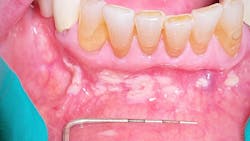

Clinical evaluation revealed scattered, white, creamy patches in the lower anterior vestibule, each measuring approximately 3–6 mm (figure 1). Now, take a look at the second picture after the white patches were easily wiped off with gauze (figure 2). Note the red, thin-membraned tissue? It was very tender to the touch and sensitive even to air.

This diagnosis should be a slam dunk—pseudomembranous candidiasis, aka thrush. Let’s have a refresher.

- Acute pseudomembranous candidiasis consists of creamy, loose patches of desquamative epithelium that are easily removed.1 Red tissue tender to the touch is what is painful to the patient.